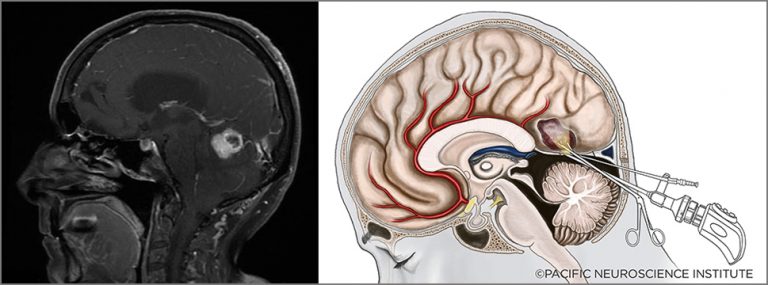

یکی از غدههای مهم بدن غده هیپوفیز است که در قاعده جمجمه و در عمق مغز قرار دارد که ممکن است دچار رشد غیرطبیعی شود. این بیماری جز تومورهای مغزی میباشد. این غده با همکاری غده هیپوتالاموس فعالیتهای مختلفی را انجام میدهد که دو نمونه از این فعالیتها شامل...